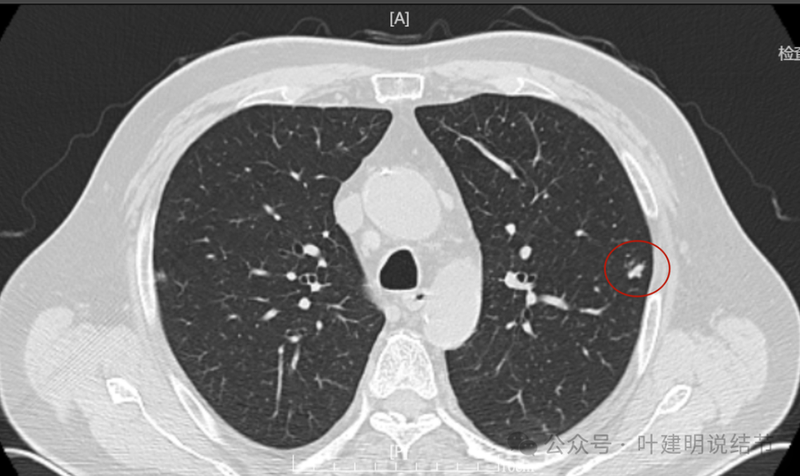

回顾看2023年10月时左上叶此处略有异常,微小实性结节,有血管与之相连。

2024年1月病灶较3个月前明显增大进展,是实性小结节,有微小血管走向病灶。

2024年5月病灶又有增大进展,实性密度,轮廓较清。

2024年9月再增大进展,见血管进入明显,靠血管这侧的边缘较为毛糙。